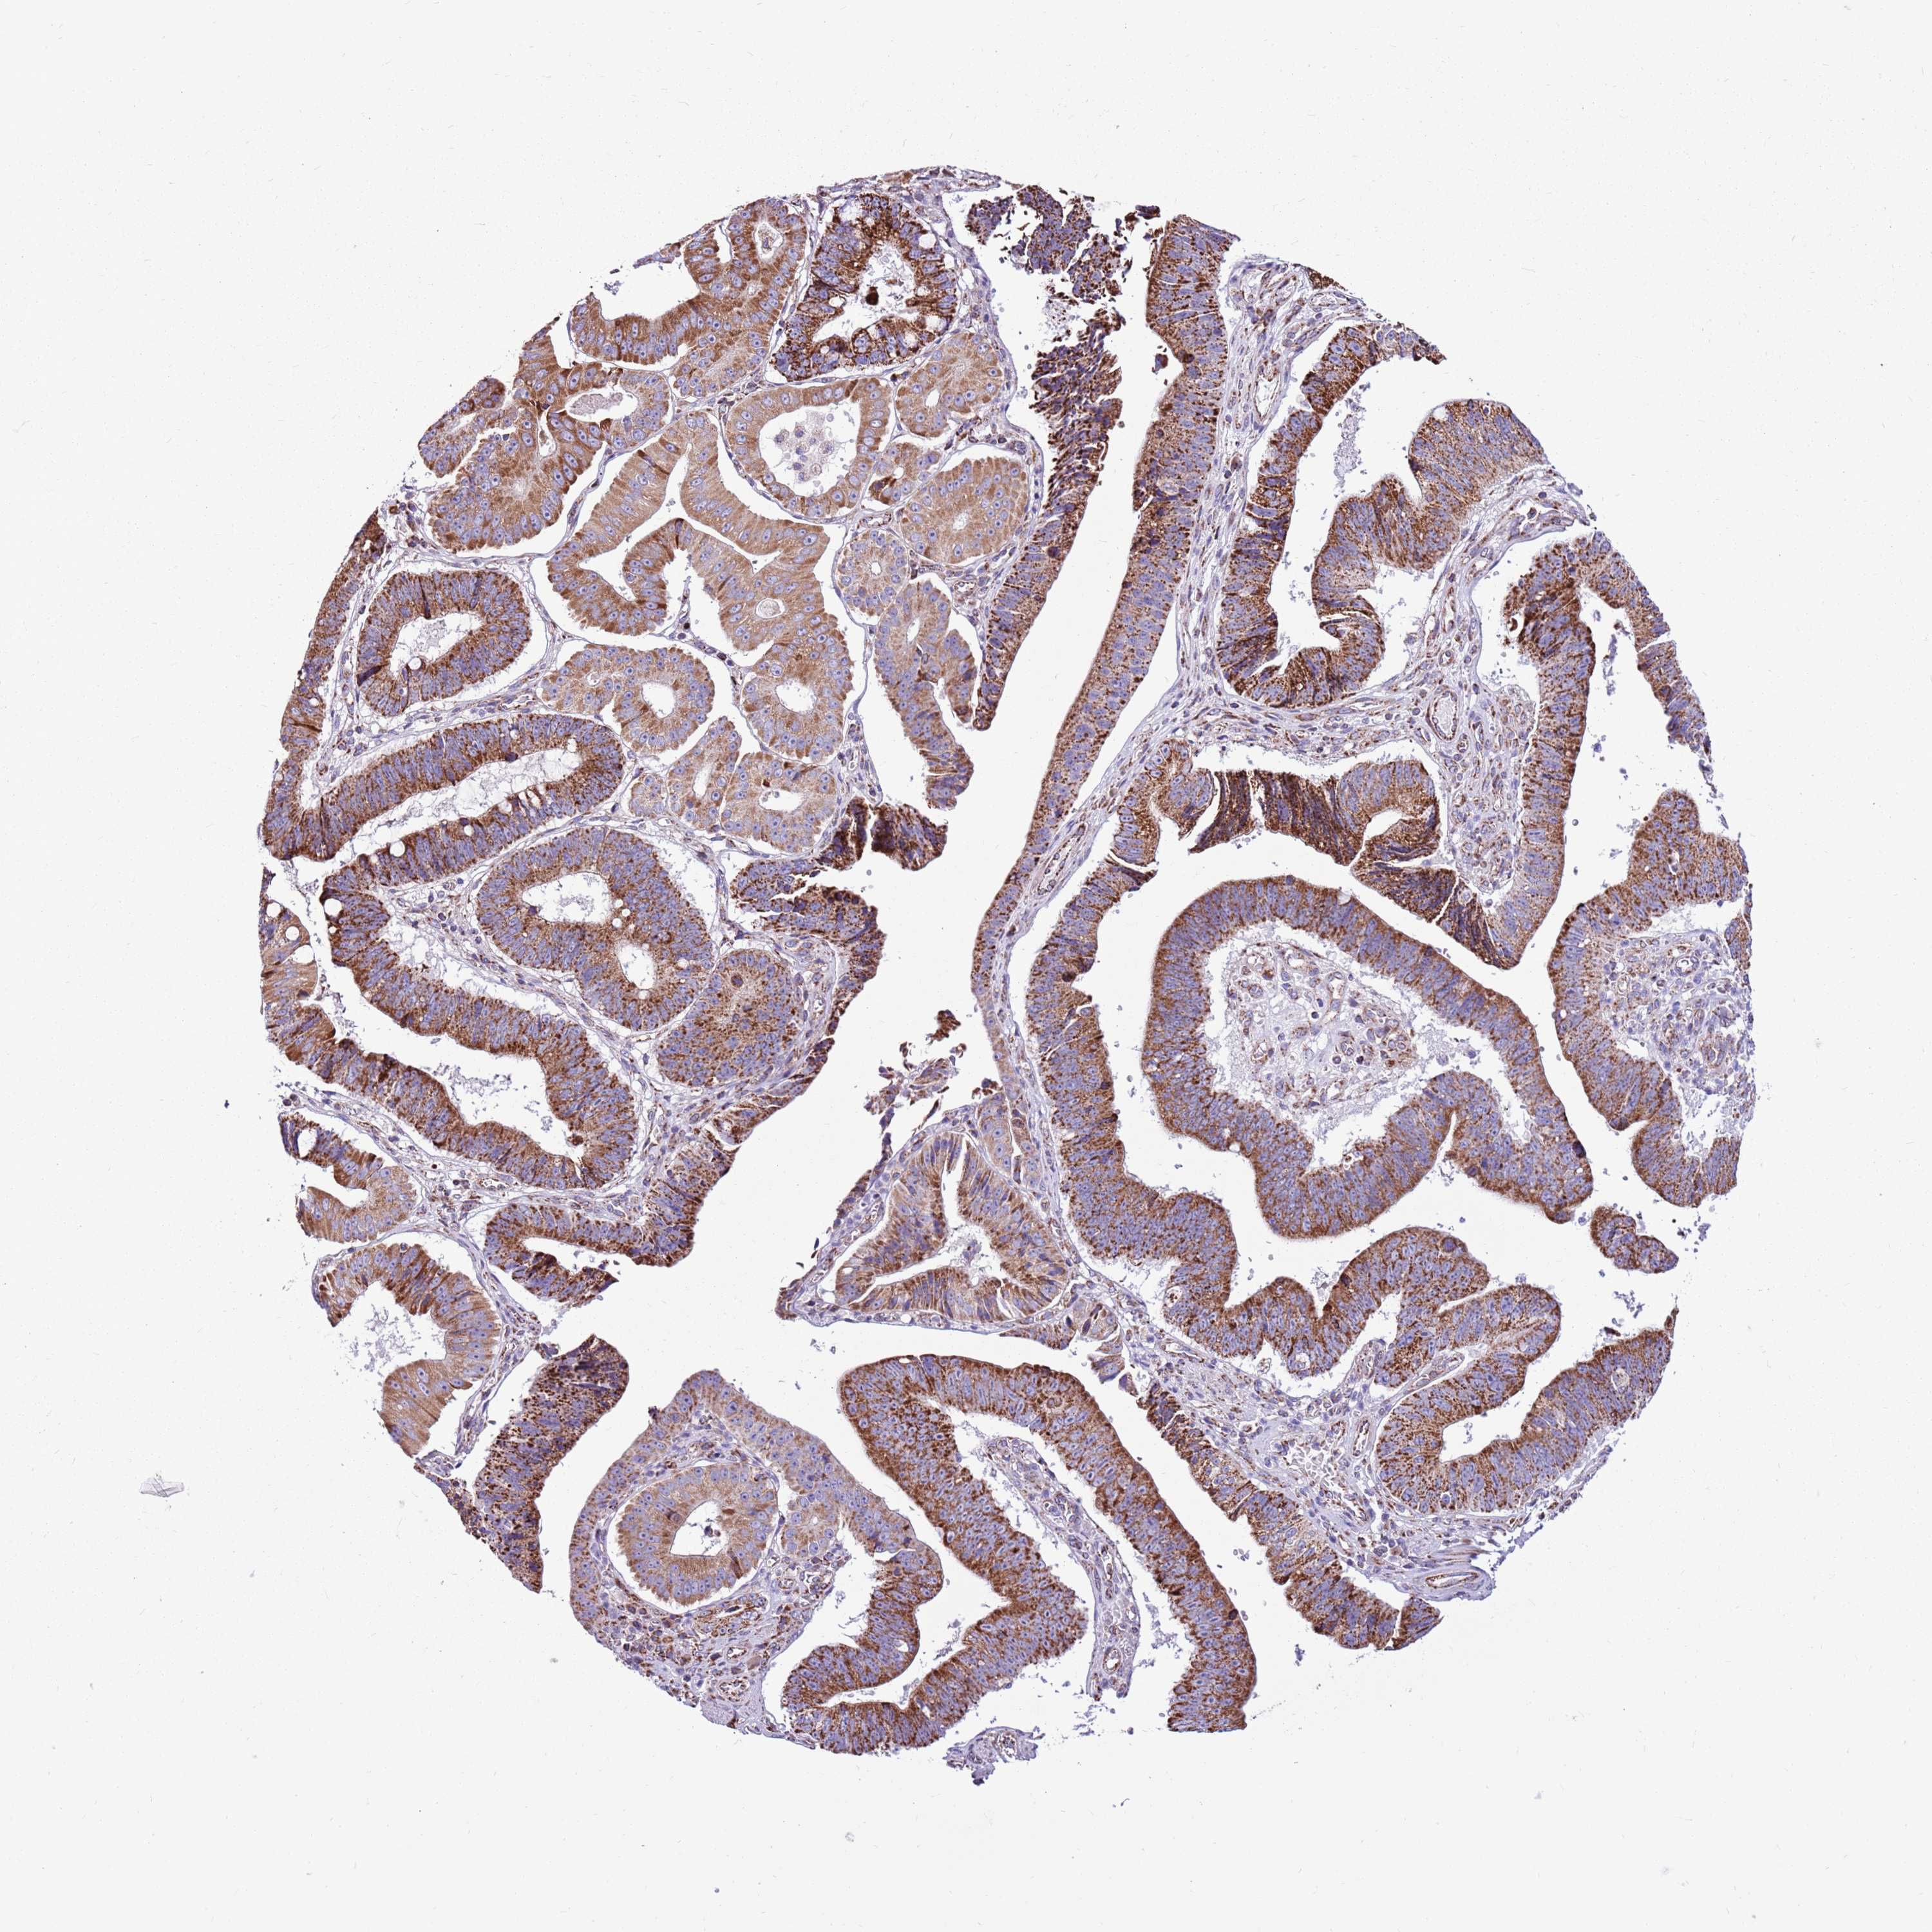

STOMACH CANCER - Protein expressioni

A mouse-over function shows sample information and annotation data. Click on an image to view it in a full screen mode. Samples can be filtered based on level of antibody staining by selecting one or several of the following categories: high, medium, low and not detected. The assay and annotation is described here.

Note that samples used for immunohistochemistry by the Human Protein Atlas do not correspond to samples in the TCGA dataset.

Antibody stainingi

Antibody staining in the annotated cell types in the current human tissue is reported as not detected, low, medium, or high, based on conventional immunohistochemistry profiling in selected tissues. This score is based on the combination of the staining intensity and fraction of stained cells.

Each image is clickable and will lead to virtual microscopy that enables deeper exploration of all samples and also displays staining intensity scores, fraction scores and subcellular localization as well as patient and tissue information for each sample.

Antibody HPA041062

Antibody HPA045473

Staining

High

Medium

Low

Not detected

Intensity

Strong

Moderate

Weak

Negative

Quantity

>75%

75%-25%

<25%

None

Location

Nuclear

Cytoplasmic/membranous

Cytoplasmic/membranous,nuclear

Adenocarcinoma, NOS